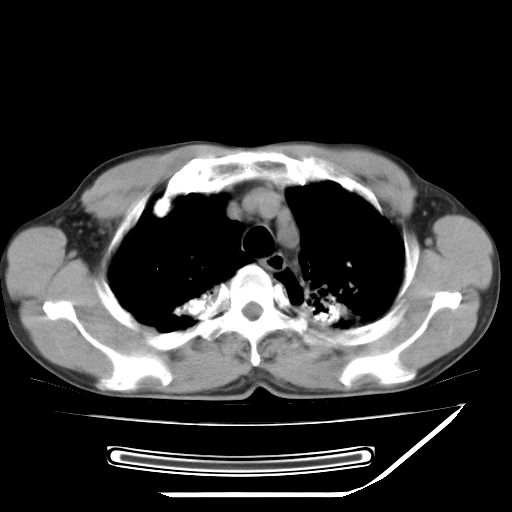

男,59岁,“结核性胸膜炎”30余年,胸部经常疼痛,多次x检查提示“肺部”炎症。腹部疼痛5日,b超提示:“肝内短管结石,余显示不清,建议进一步检查。”

两肺结核并右侧胸腔积液;脾脏、腹腔及腹膜后淋巴结结核[陈旧性];肝内胆管结石

胸部腹部都是结核(双肺。纵隔淋巴结,肝脏,脾脏,肠系膜)

均为结核所致,右侧少量胸腔积液